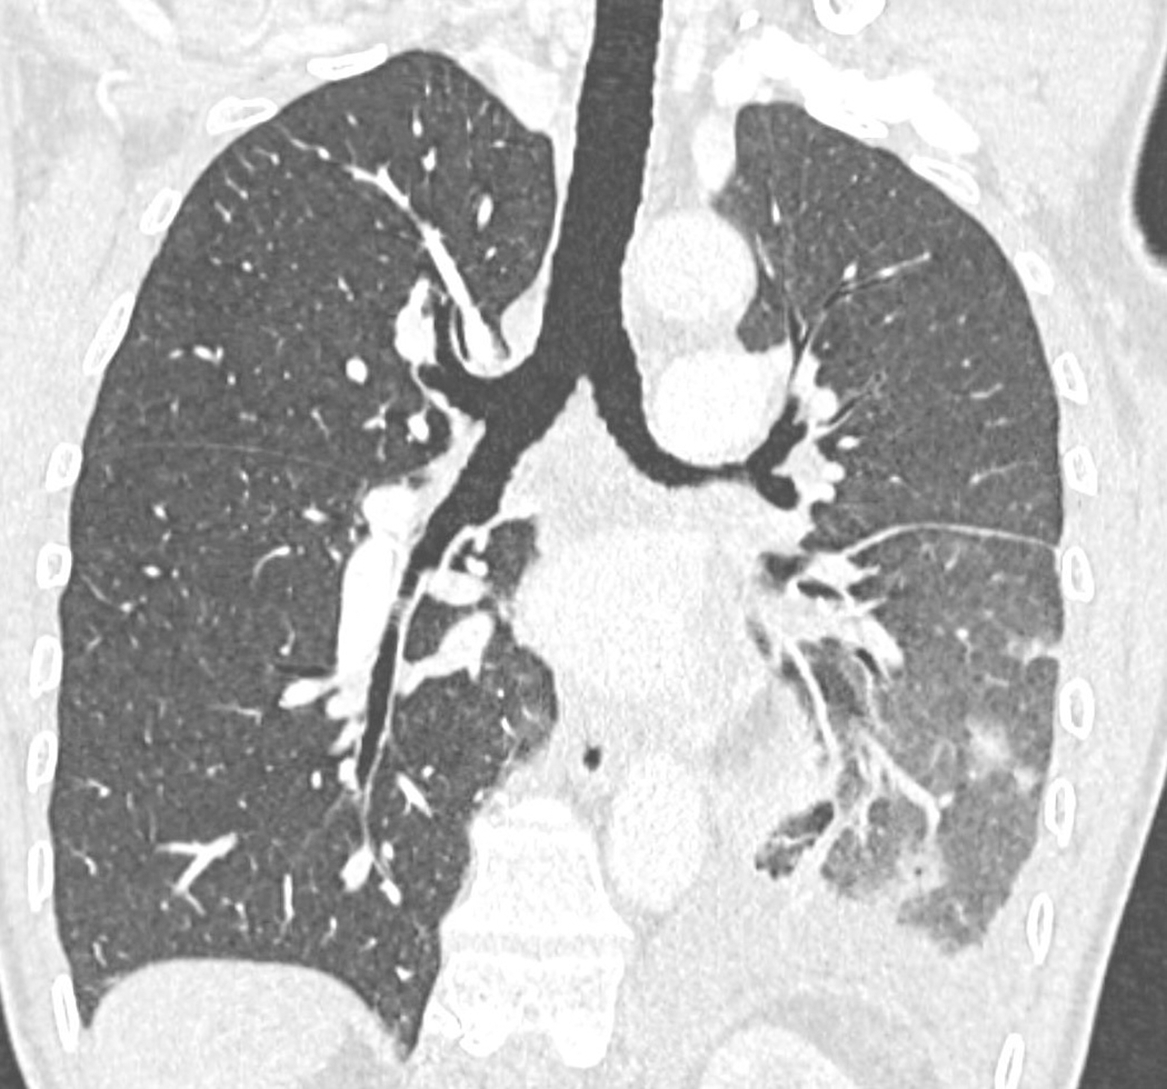

Figure 1

Contrast‑enhanced coronal chest CT (pulmonary window) with unilateral left signs of patchy alveolar hemorrhages, pulmonary edema, and pleural effusion.